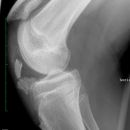

Kniegelenk